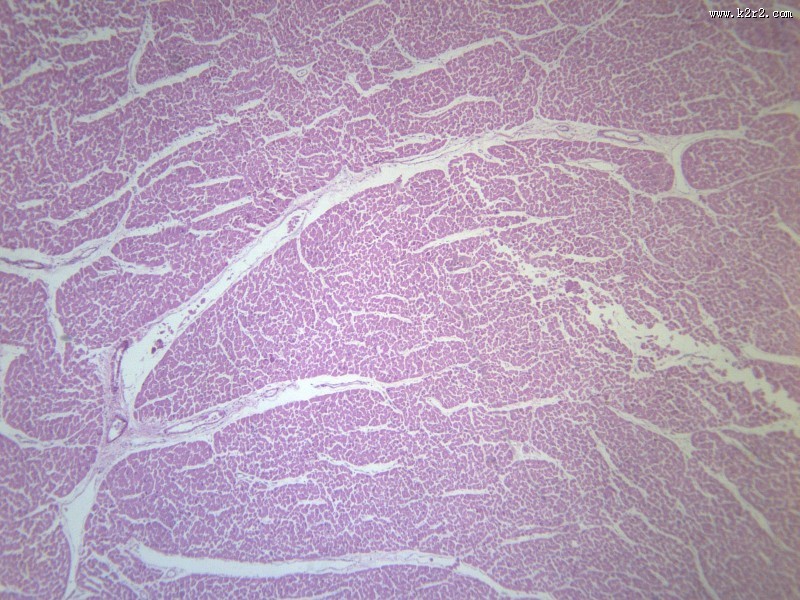

风湿性心肌炎 - 第3张

风湿性心肌炎

图集中 / 共有 12 张图片

心肌炎